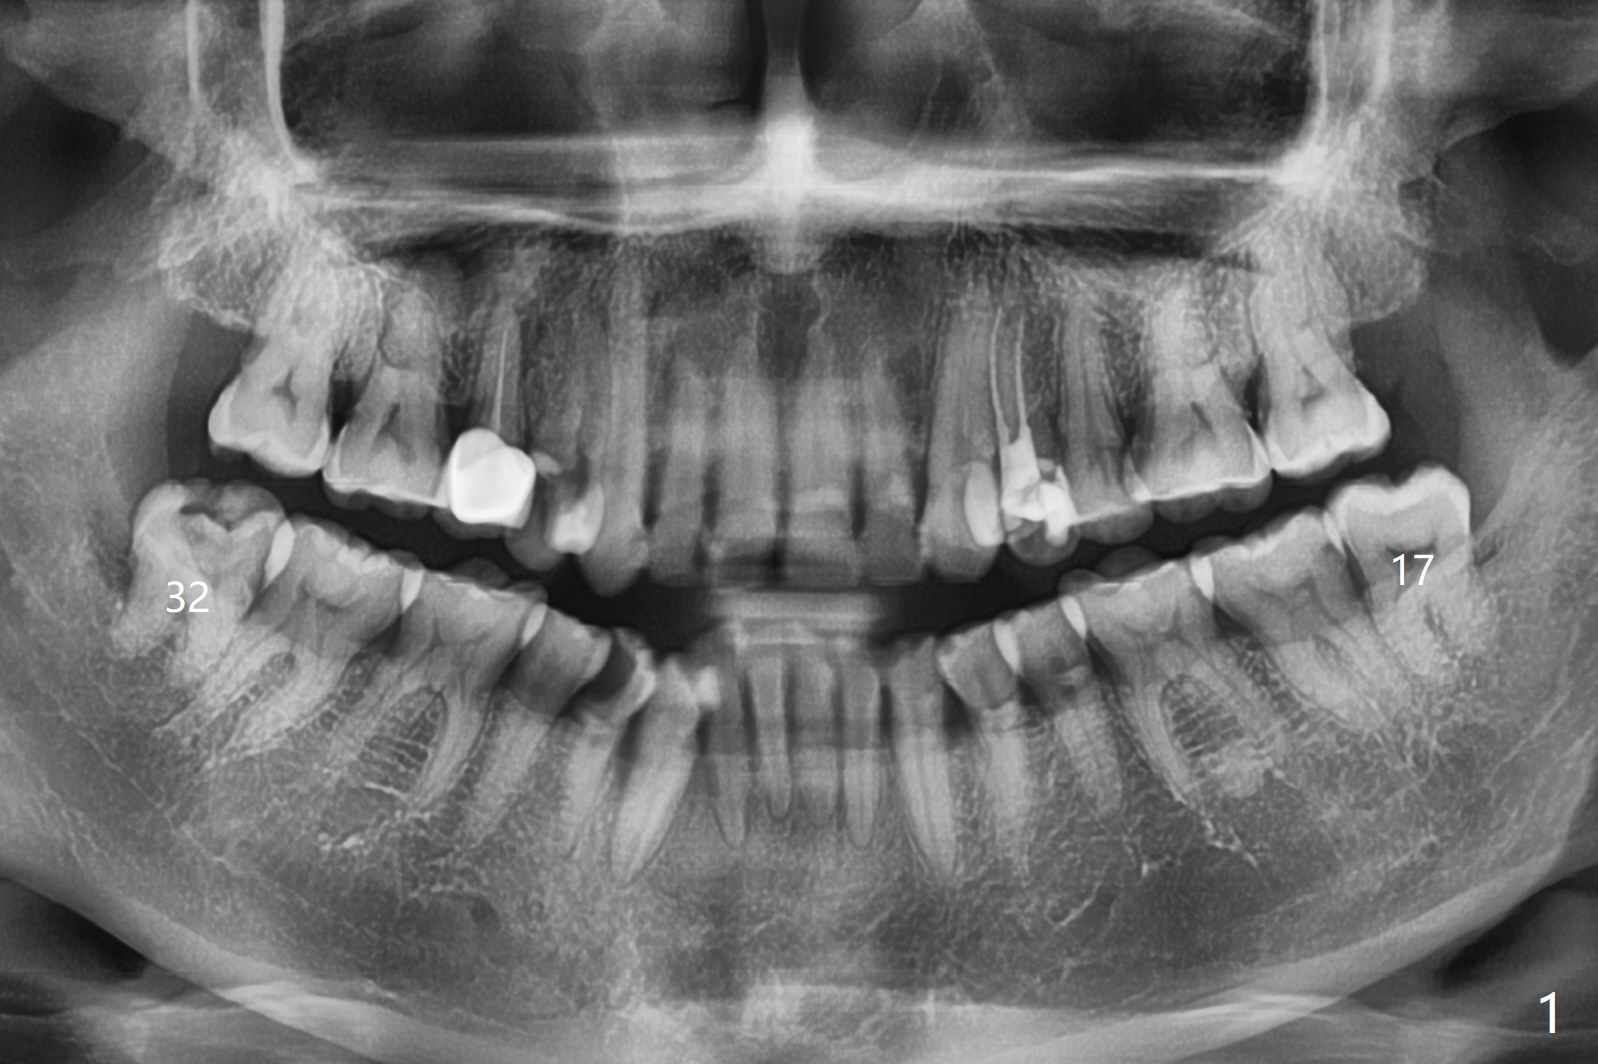

A 52-year-old woman agrees to have #17 and 32 removed (due to caries) with 4q SRP (Fig.1). #17 needs incision for elevation between the buccal crest and the root before application of forceps.